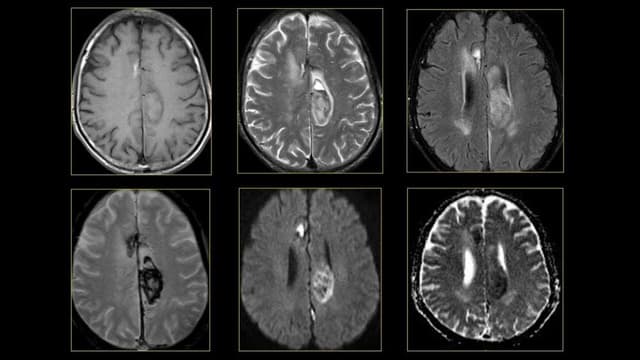

Chụp MRI mạch máu não có tác dụng gì, khi nào cần thiết?

Chụp MRI mạch máu não hay chụp cộng hưởng từ mạch não là phương pháp chẩn đoán hình ảnh hiện đại đóng vai trò hàng đầu trong chẩn đoán các bệnh lý về thần kinh và não hiện nay. Chụp MRI mạch não cho thấy rất nhiều ưu điểm rõ rệt như tính an toàn […]